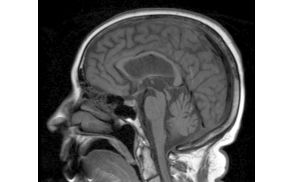

Predavala bo dr. Milica Gregorič Kramberger, specialistka nevrologije, ki je zaposlena na Univerzitetnem kliničnem centru Ljubljana, Nevrološka klinika, Ambulanta za kognitivne motnje.

Predavanje je povezano z boleznijo sodobnega časa demenco - izgubo spomina, ob kateri se pojavlja veliko vprašanj, na katera pogosto ne poznamo odgovora.